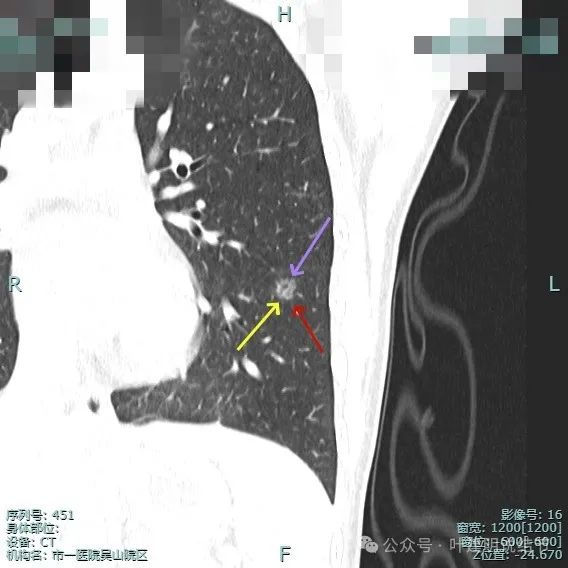

病灶密度仍纯但不太均匀,整体轮廓与瘤肺边界清。

有小血管进入与类反晕征。

血管进入以及轮廓与边界清楚。

密度不均显杂乱。